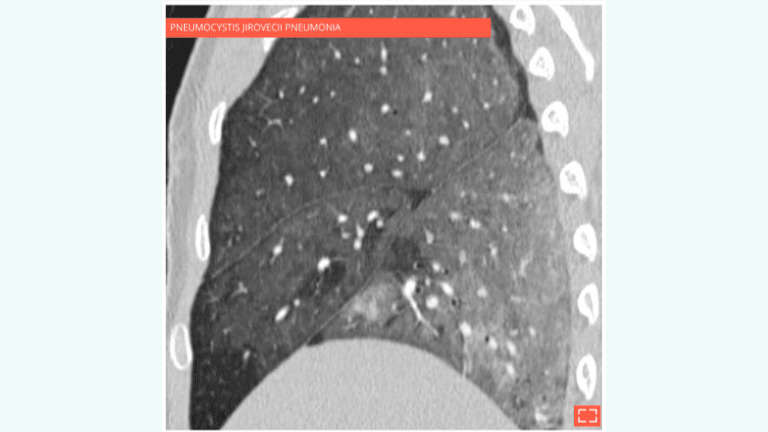

•  Slightly increased attenuation of lung parenchyma, with preservation of vascular and bronchial margins.

• Ground-glass opacity can be associated with various conditions:

• Pulmonary infection: pneumocystis jirovecii pneumonia, cytomegalovirus (CMV), etc.